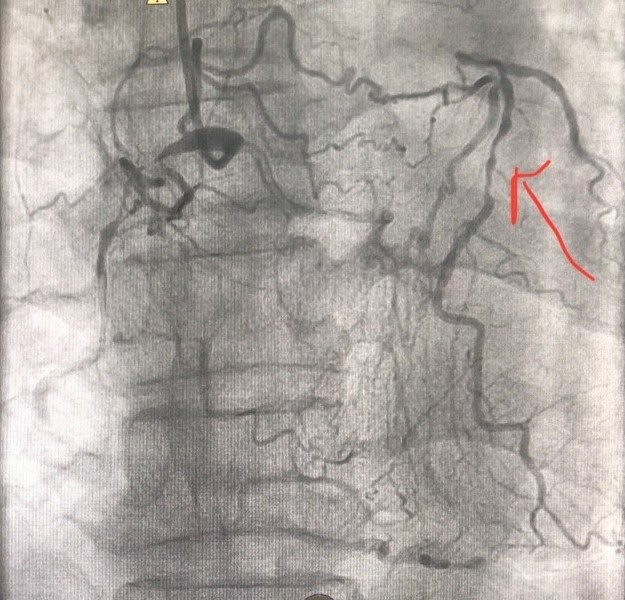

Sau khi hội chẩn, các bác sĩ Khoa Can thiệp Tim và mạch máu đã thống nhất tiến hành can thiệp đặt stent động mạch vành cho người bệnh. Sau 2 lần thực hiện phương pháp can thiệp động mạch vành, các bác sĩ đã tái thông và đặt stent 2 nhánh mạch lớn là động mạch vành phải và động mạch mũ bên trái. Sau can thiệp 5 ngày tình trạng của người bệnh ổn định, có thể tự đi bộ, leo cầu thang và không còn những cơn đau ngực khi gắng sức. Người bệnh đã được xuất viện và tái khám định kỳ.

Với tiến bộ của y học, các thế hệ stent mới có cấu trúc mỏng hơn, phủ thuốc chống tái hẹp tốt hơn và trình độ của bác sỹ làm can thiệp ngày càng được nâng cao, người bệnh tắc cả 3 nhánh động mạch vành đã được can thiệp thành công với kết quả tốt, không xảy ra tai biến, biến chứng cũng như tránh cho người bệnh một cuộc phẫu thuật mổ tim mở bắc cầu nối chủ – vành tiên lượng nặng nề hơn và thời gian hậu phẫu, hồi phục kéo dài hơn rất nhiều.